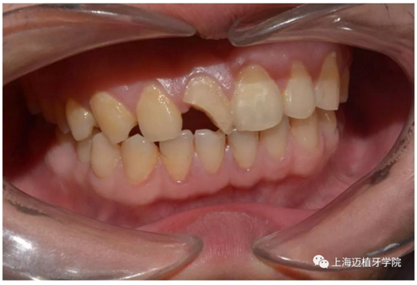

術(shù)前照片

主訴:前門(mén)外傷牙根折要求修復(fù)?現(xiàn)病史:前門(mén)牙外傷,劈裂至根部,無(wú)法固定及其他修復(fù),要求種植?檢查:11牙冠2/3缺損,唇腭向劈裂,唇部紅腫。 CT示根折, 骨寬度9.47mm,距鼻底12.34mm,Ⅲ類骨。 口腔衛(wèi)生一般